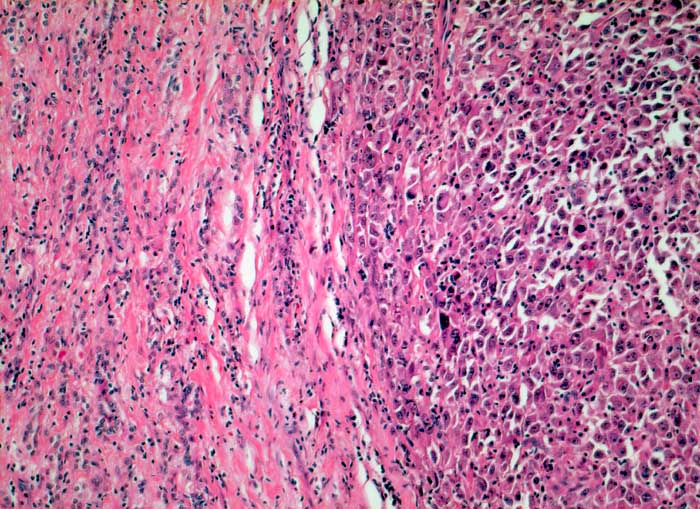

Anaplastisches Schilddrüsenkarzinom

Anaplastischer solider Tumorknoten mit bizarren grossen Tumorzellen.

Strumaknoten links mit Einengung der Trachea

Histologie

100